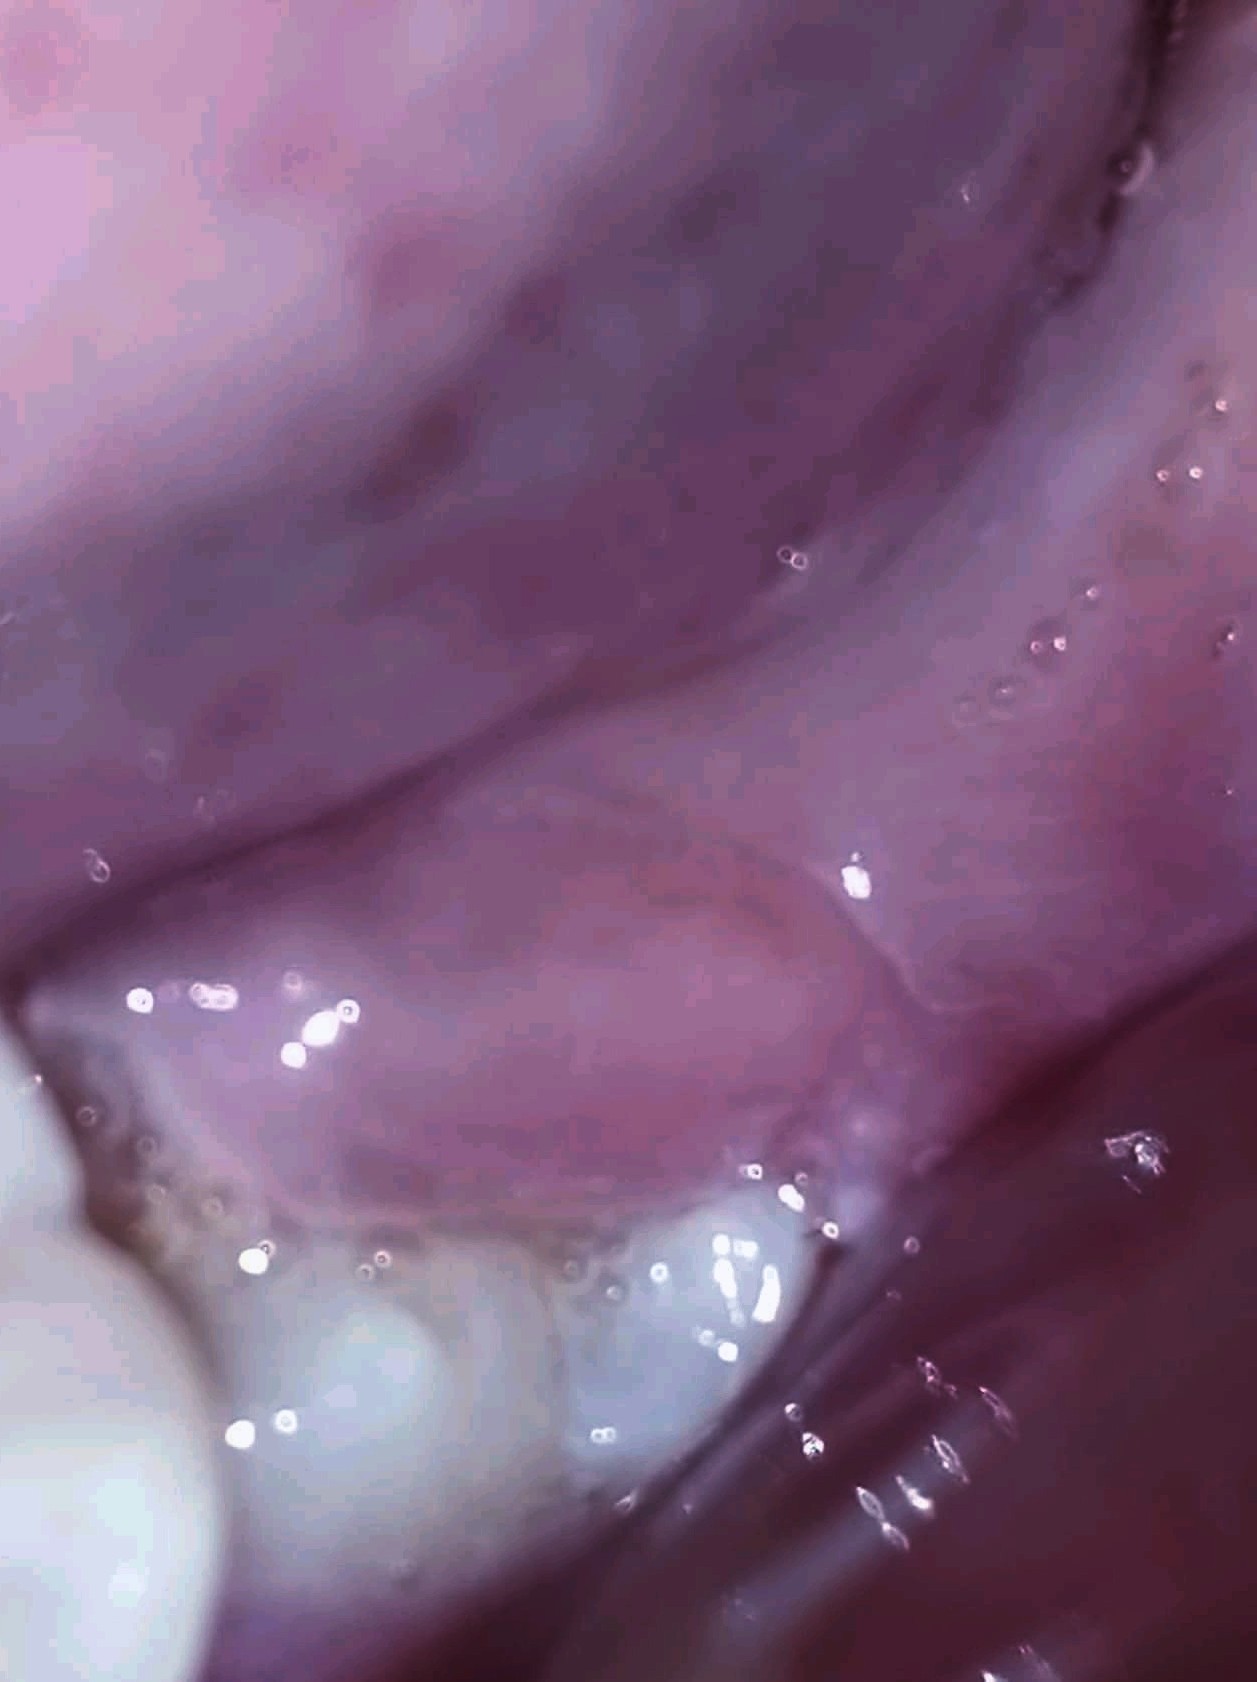

ضرسي العقل في الفك السفلي نصفه بارز ونصفه الاخر مغطى باللثة ، ومنذ يومين عانيت من احمرار اللثة بجانبه بالاضافة لصداع و دوخة والم في الاذن بجواره مع الام في الفكين العلويين ،

علما انه ليس اسود ومعمودي ومنتظم ولا يوجد فيه نخر ، هو لا يؤلمني لكني اشعر ان الخد متورم بالاضافة للاعراض المذكورة فوق

• PicsArt_01-18-07.48.48.jpg

PicsArt_01-18-07.48.48.jpg